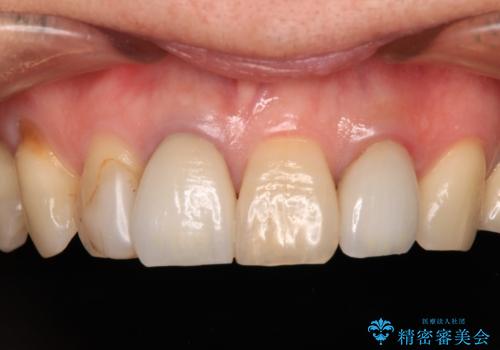

変色した前歯 ジルコニアクラウンでの修復

前歯の黒い縁を綺麗にしたい 前歯のオールセラミック